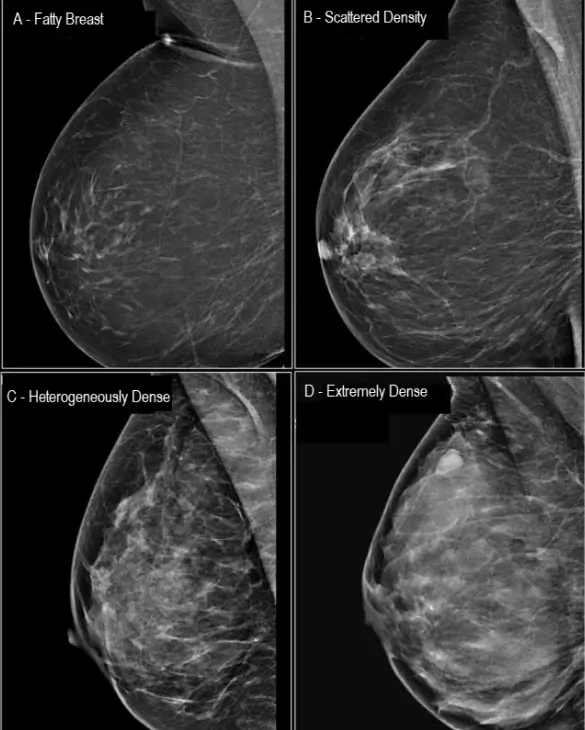

Radiologists are required to notify patients of density as part of their mammography report. Read the report carefully and or ask your doctor. Look for any descriptions of your breast tissue density. Sometimes the report will indicate a density category (A to D) or utilize associated words to describe the level of density as determined by the radiologist

A - Fatty (Non-Dense)

B - Scattered Density (Non-Dense)

C - Heterogeneously Dense (Dense Breasts)

D - Extremely Dense (Dense Breasts)

On a mammogram, fatty tissue appears dark and transparent. Dense tissue appears as a solid white area, which makes it difficult for the radiologist to see through.

Cancer and dense breast tissue appear white on a mammogram. This increases the chance that breast cancer will go undetected.